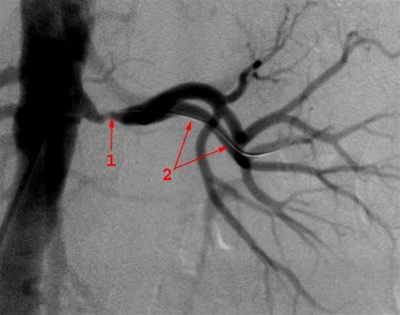

Afsluttende arteriografi efter dilatation af stenose i nyrearterien med 5 mm ballon - perkutan transluminal renal angioplastik (PTRA). Ballonen er fjernet, mens guide-wire stadig ligger i nyrearterien. Røntgenkontrastvæske viser at forsnævringen er ophævet.